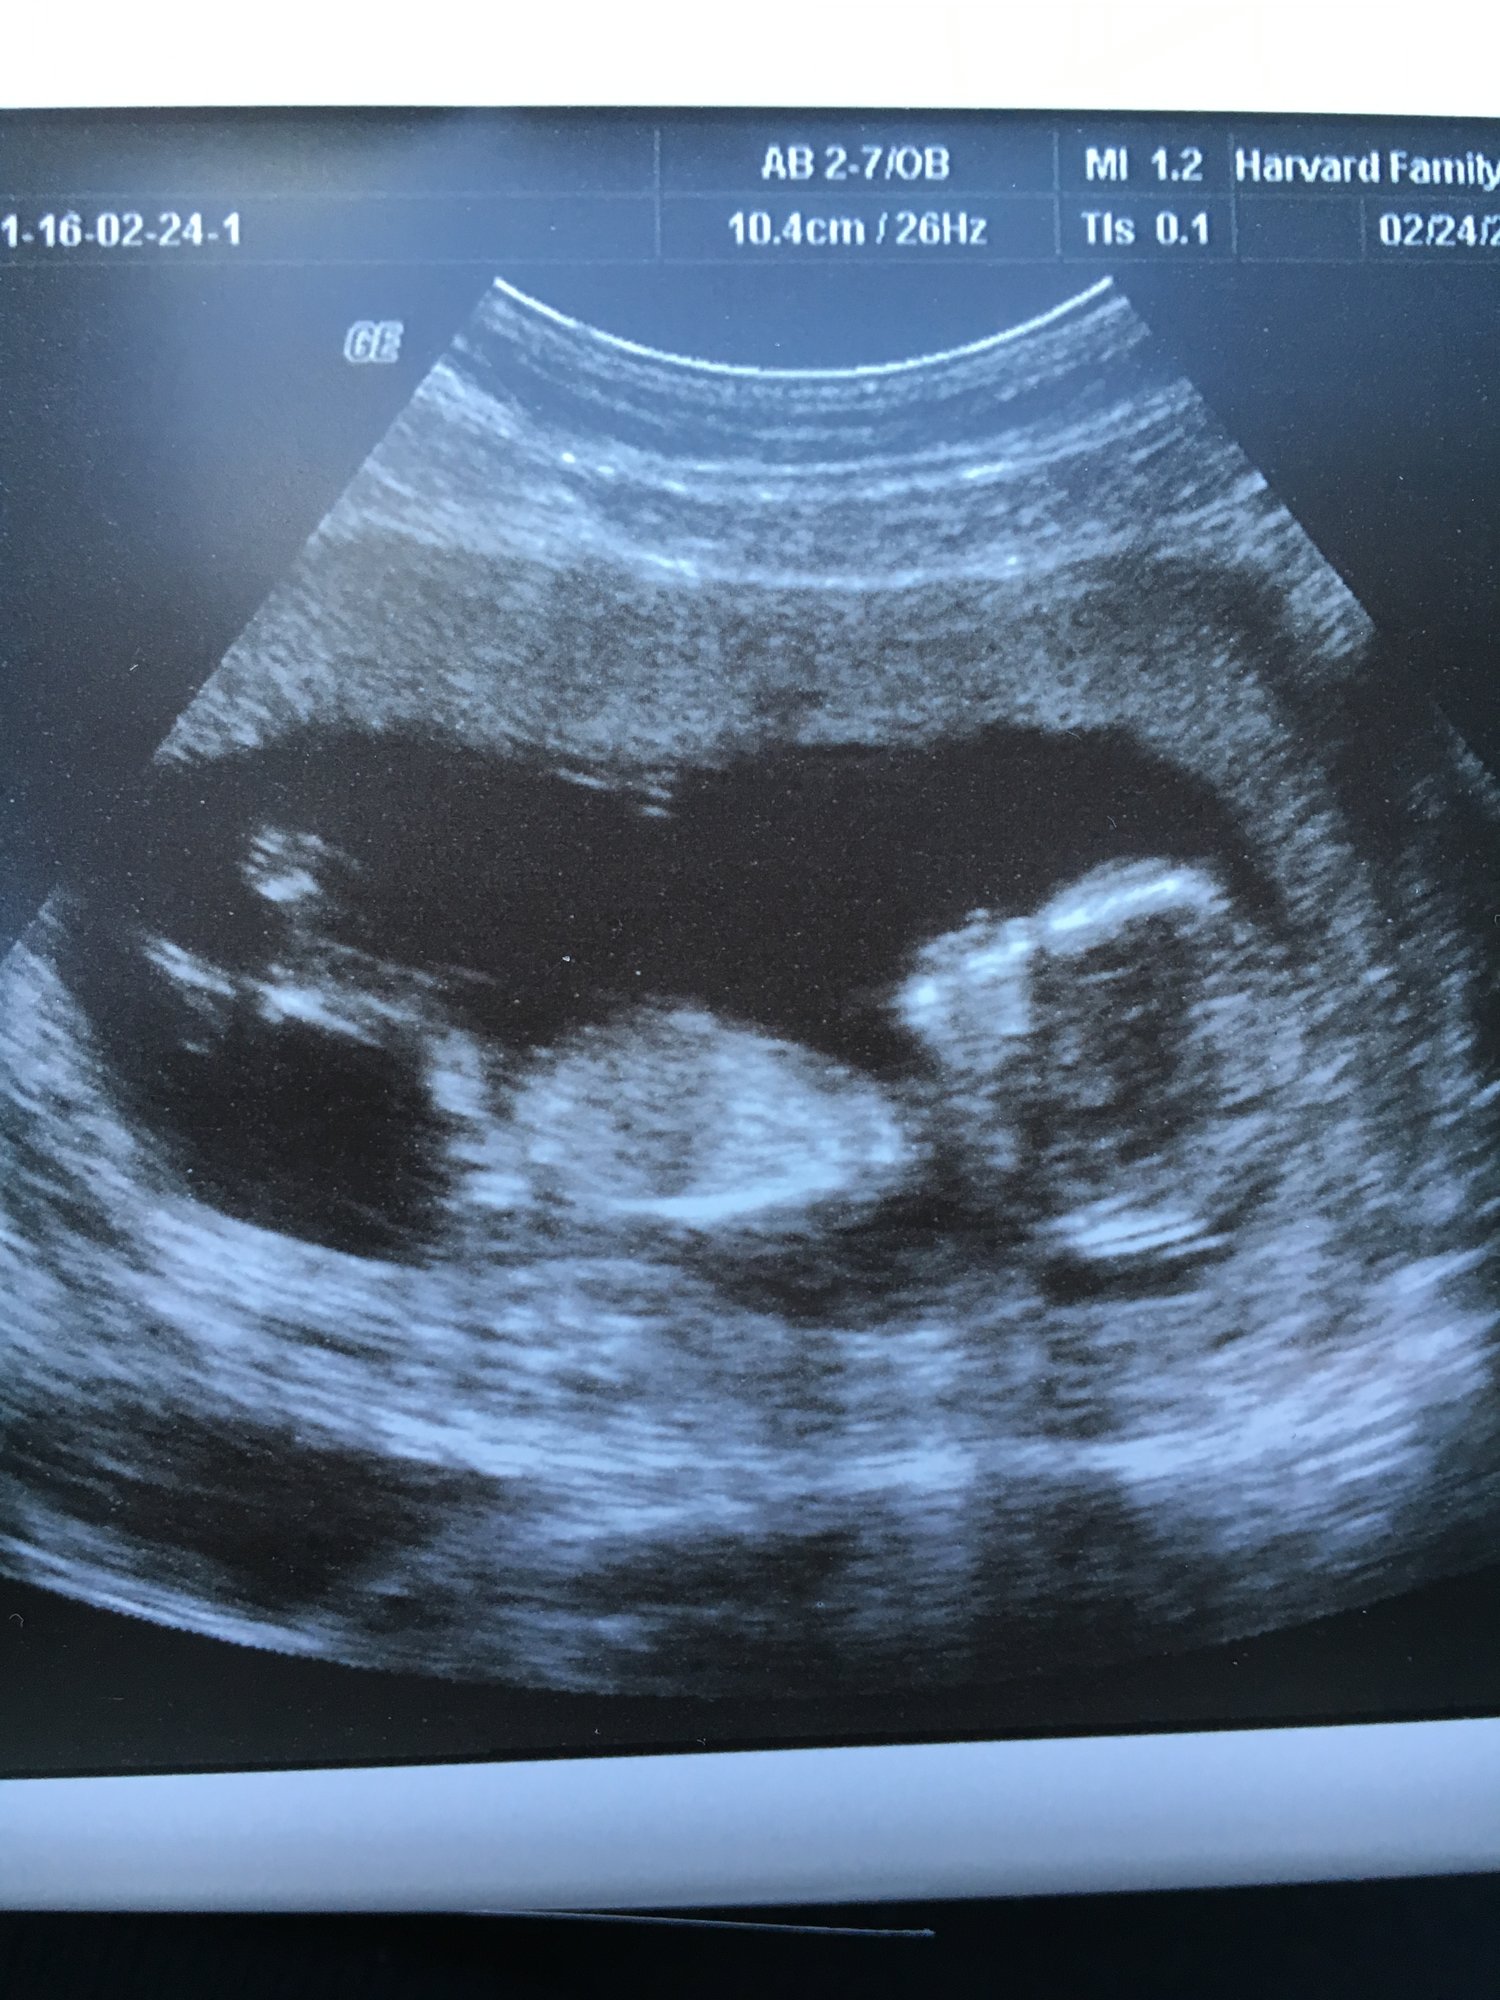

Our little baby!! 12 weeks 4 days and actually looking like a baby now it was so fun getting to watch it move around! This is my first pregnancy and due date is September 3rd!